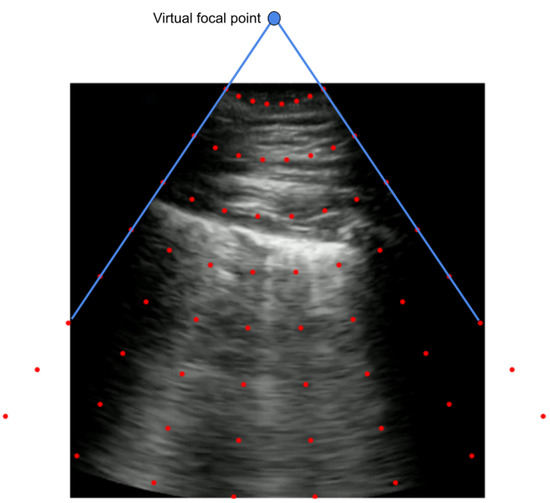

An alternative approach to employing a projective transformation would be utilizing a piecewise affine transformation. In this case, rather than a single transformation matrix that would be applied to the entire image, a number of affine transformations are estimated for different sections of the image based on a grid of points. The grid of points is generated by first locating the virtual focal point, after which the grid is established using polar coordinates originating from that center point as a distance and angle. This implementation assumes circular radiation from the center. This grid is generated for each new and old group of corner points. Visualization of such a grid can be seen in Figure 5.

The virtual focal point is calculated finding the point which intersects with the two lines defined by the left and right bounds of the angled viewing window. A random transformation is sampled similarly to the projective transform through finding new corner points, as shown in Figure 3.

Figure 5. An example grid of points for constructing a piecewise affine transform.